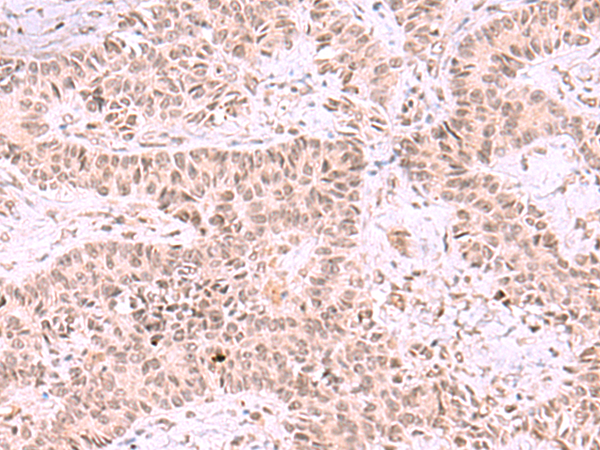

分类: 科研抗体货号: P11046别名: FRAP, FRAP1, FRAP2, RAFT1, RAPT1应用: IHC反应种属: Human, Mouse, Rat